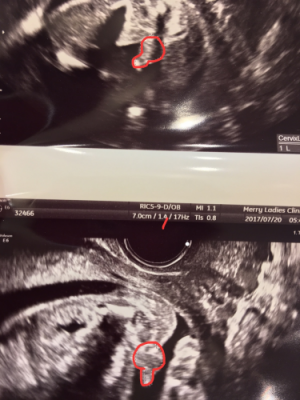

4dエコー画像 12週 手足、へその緒が見えてきました。まだ2頭身です。 14週 3頭身になってきました。 17週 全身が一画面にかわいく写る週数です。 18週 リアルモードだと本当にお腹の中をのぞいているよう! 21週妊娠6ヶ月で性別が判明妊娠週~23週 女の子は妊娠7ヶ月で判明が多い妊娠24週~26週 妊娠8ヶ月で可能性が確実に! ? 妊娠28週・30週 中には妊娠9ヶ月まで隠していた男の子も妊娠33週・34週 妊娠4ヶ月のエコーで分かる場合も妊娠15週19/7/19 週の男の子のエコー写真 周りの羊水で少し見づらいですが、左側がお尻、右側が足になります。 真ん中にちょこんとシンボルがうつっているのがわかりますでしょうか。 22週の男の子のエコー写真 22周めの男の子の写真です。